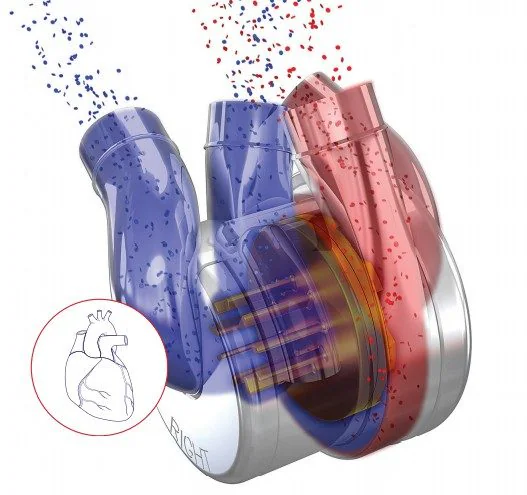

Το δίδυμο πατέρας-γιου εργάστηκε ακούραστα στο οικογενειακό τους σπίτι στο Μπρίσμπεϊν της Αυστραλίας για να κατασκευάσουν ένα πρωτότυπο που τελικά εξελίχθηκε στην πρώτη ανθεκτική τεχνητή καρδιά – μια μηχανική αντλία αίματος από τιτάνιο.

Η συσκευή, κατασκευασμένη από την εταιρεία του Timms, BiVACOR, με το μοναδικό μέταλλο που δεν απορρίπτεται από τον ανθρώπινο οργανισμό, έγινε παγκοσμίως γνωστή τον προηγούμενο μήνα όταν αποκαλύφθηκε πως ένας ασθενής στο Σίδνεϊ έγινε ο πρώτος άνθρωπος στον κόσμο που πήρε εξιτήριο από νοσοκομείο με τη συσκευή εμφυτευμένη.

Το δίδυμο πατέρας-γιου εργάστηκε ακούραστα στο οικογενειακό τους σπίτι στο Μπρίσμπεϊν της Αυστραλίας για να κατασκευάσουν ένα πρωτότυπο που τελικά εξελίχθηκε στην πρώτη ανθεκτική τεχνητή καρδιά – μια μηχανική αντλία αίματος από τιτάνιο.

Η συσκευή, κατασκευασμένη από την εταιρεία του Timms, BiVACOR, με το μοναδικό μέταλλο που δεν απορρίπτεται από τον ανθρώπινο οργανισμό, έγινε παγκοσμίως γνωστή τον προηγούμενο μήνα όταν αποκαλύφθηκε πως ένας ασθενής στο Σίδνεϊ έγινε ο πρώτος άνθρωπος στον κόσμο που πήρε εξιτήριο από νοσοκομείο με τη συσκευή εμφυτευμένη.